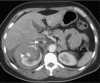

Angiomyolipomas (AMLs) are the most common benign renal tumours. Most of these neoplasms are found incidentally on imaging. However, symptomatic presentation does exist. Renal AMLs are typically composed of smooth muscle, blood vessels, and adipose tissue. Because of the abundant fat tissue, they give a characteristic appearance on imaging and are therefore easily diagnosed. However, sometimes they contain too little fat to be detected. This increases the difficulty in differentiating them from renal cell carcinoma (RCC). Management of AML is based on clinical presentation and should be individualized for every patient. Treatment modalities range from active surveillance to more invasive approaches.